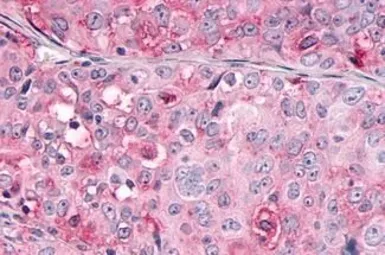

OR10R2 antibody

Cat. No. GTX71527

ApplicationsIHC-P

ReactivityHuman, Rabbit, Bovine, Monkey